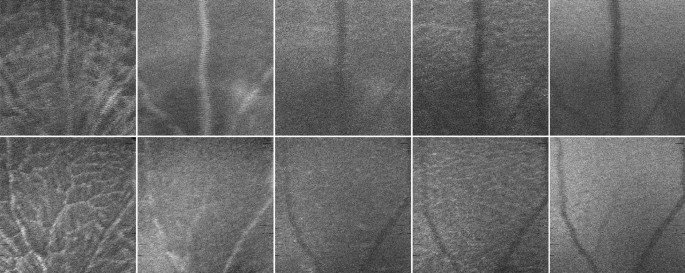

The retinas of both eyes of wild type (WT) (C57BL6/129S) and 3xTg-AD mice were imaged using a Micron IV OCT System (Phoenix Technology Group, Pleasanton, CA, USA) at the ages of 11 (weight: 14.9 ± 2.6 g), 2 (weight: 22.4 ± 2 g), 3 (weight: 25.4 ± 2.1 g), 4 (weight: 27.2 ± 2.1 g), 8 (weight: 31.6 ± 3.4 g), and 12-months-old (weight: 33.5 ± 3.8 g). Volumes with insufficient image quality, low contrast, or leading to segmentation errors were excluded from the dataset. Also, from the initial 57 WT and 57 3xTg-AD mice, respectively, 7 and 13 deceased over the time window of the study (mice died between the ages of 1–2 (4 WT and 1 3xTg-A), 2–3 (1 3xTg-A), 3–4 (2 3xTg-A), 4–8 (2 WT and 4 3xTg-A) and 8–12 (1 WT and 5 3xTg-A)). For the remaining volumes, OCT data was segmented as disclosed in16 to compute five mean value fundus (MVF) images (Fig. 1) corresponding to retinal layers/layer-aggregate of the neuroretina: the retinal nerve fibre layer and ganglion cell layer complex (RNFL-GCL), the inner plexiform layer (IPL), the inner nuclear layer (INL), the outer plexiform layer (OPL), and the outer nuclear layer (ONL). In MVF images18, each pixel’s value is the average of the respective A-scan values within the boundaries of the layer of interest, therefore mimicking a fundus photograph if taken in the absence of all remaining layers.

MVF (mean-value fundus) images examples from two left eyes of mice two months old (top: WT, bottom: 3xTg-AD). From left to right: RNFL-GCL (retinal nerve fibre layer-ganglion cell layer) complex, IPL (inner plexiform layer), INL (inner nuclear layer), OPL (outer plexiform layer), and ONL (outer nuclear layer).